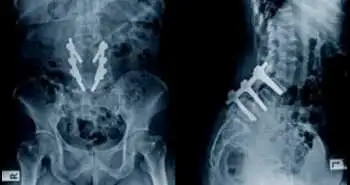

This study was conducted to find the functional and radiographic outcomes in adolescents treated for thoracic idiopathic scoliosis using pedicular screws, with the follow-up of an average 20 years.

In this study, 109 patients were inspected. The radiographic data were assessed on fullspine radiographs (thoracic kyphosis, Cobb angle, pelvic tilt, lumbar lordosis, pelvic incidence). The Clinical data were assessed with Analog Pain Scale ODI, SRS-30 and SF-12. Listhesis below the arthrodesis and disc height were calculated.

Radiographic data were evaluated for 46 patients after 17.4 years. Mean Cobb angle was 58° before the surgery, and there was a mean correction of 40.1% with a loss of 5.3° at the final follow-up. Thoracic kyphosis and lumbar lordosis rose considerably at end follow-up.

It was concluded that there is an improvement in very long-term clinical and radiographic results after posterior spinal fusion using pedicular screws for the treatment of thoracic adolescent idiopathic scoliosis.